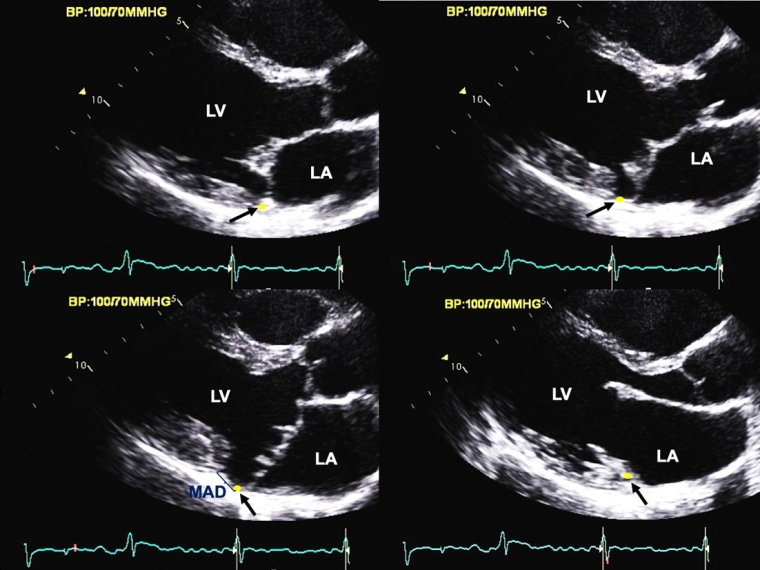

MAD, in the clinical setting, is characterised by macroscopic detachment of the mitral annulus supporting the posterior mitral leaflet from adjacent ventricular myocardium [20]. Hence, MAD is associated with partial loss of mechanical annular function which is dependent on its normal ventricular myocardial attachment while electrical isolation of the left atrium/ventricle is maintained [10,21]. MAD is predominantly observed at the insertion site of the posterior physiologic leaflet, extending laterally variably under all scallops but preferentially under the P2 scallop. MAD is not uniformly observed in MVP, detectable by echocardiography in approximately 1/3 of patients [10]. While MAD has been hypothesised as causing MVP, its inconsistent presence argues in favour of MAD and MVP being variable consequences of myxomatous degeneration. Diagnosis requires high spatial/temporal resolution imaging, in long-axis views by transthoracic echocardiography [22] or MRI [7] through dynamic frame-by-frame analysis with careful examination of mitral annulus position [8] (Figure 3). MAD depth measurement begins at the posterior leaflet insertion site on the annulus/left atrial wall, and ends at the detached LV myocardium in systole [7,23]. MAD may occur in any form of MVP, but is most common in advanced myxomatous degeneration with bileaflet MVP, with longer, thicker and redundant leaflets, larger mitral annulus, independent of all other characteristics [7,10]. The term “curling” is used to refer to the deformation of the posterior leaflet assumed to remain attached to the ventricular myocardium but we find it a misnomer as the annulus is almost completely detached from the myocardium with MAD [24]. Emerging data suggest that tricuspid annulus disjunction may coexist with MAD [25].

Figure 3. Frame-by-frame analysis of the mitral apparatus by transthoracic echocardiography in a parasternal long-axis view within the entire cardiac cycle.

(Upper-row left) The yellow dot with the single black arrow characterises the position of the posterior mitral annulus in early systole and (upper-row right) mid-systole. Note the prolapse of the mitral leaflets appearing in mid-systole, more pronounced on the posterior leaflet, and the absence of posterior annular disjunction yet. (Lower-row right) Late systole view showing bileaflet MVP with MAD (single blue arrow) defined as a detachment of the posterior mitral annulus (yellow dot/single black arrow) from the adjacent LV myocardium. (Lower-row right) Early diastole view showing restored continuity between the insertion site of the posterior leaflet on the mitral annulus and the LV myocardium, emphasising the necessity of image-by-image analysis of the mitral valve for MAD measurement in end systolic view after identification of the insertion of the posterior MV leaflet in early systole.

LV: left ventricle, MAD: mitral annulus disjunction; MV: mitral valve; MVP: mitral valve prolapse

Reproduced with permission from the figures of Eur Heart J 44(33): 3121-3135.